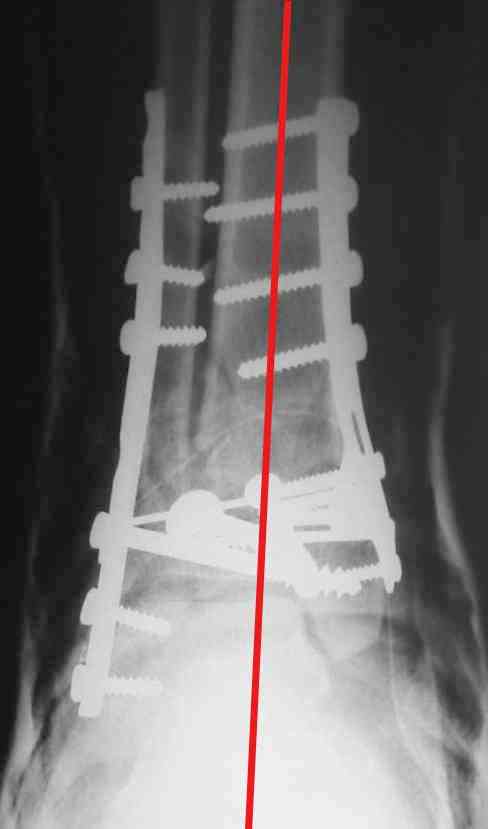

Re: Perelom N/3 kostei goleny

ДВ> Очень прилично получилось, но мне показалось, что винты на 4,5 мм.Это

ДВ> принципиально винты используются 3,5 и 4,0 мм.

А чем чревато использование обычных кортикальных винтов 4,5 мм с не-LCP пластинками?

ДВ> И проекцию прямую бы переделать.

А зачем ее переделывать?

На представленном снимке видно, что эпифиз смещен латерально.

Сейчас с этим ничего не сделать, похоже.